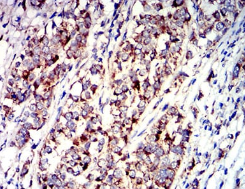

P2RY1 Mouse Monoclonal antibody[4G5D6]

IHC    1/200 - 1/1000